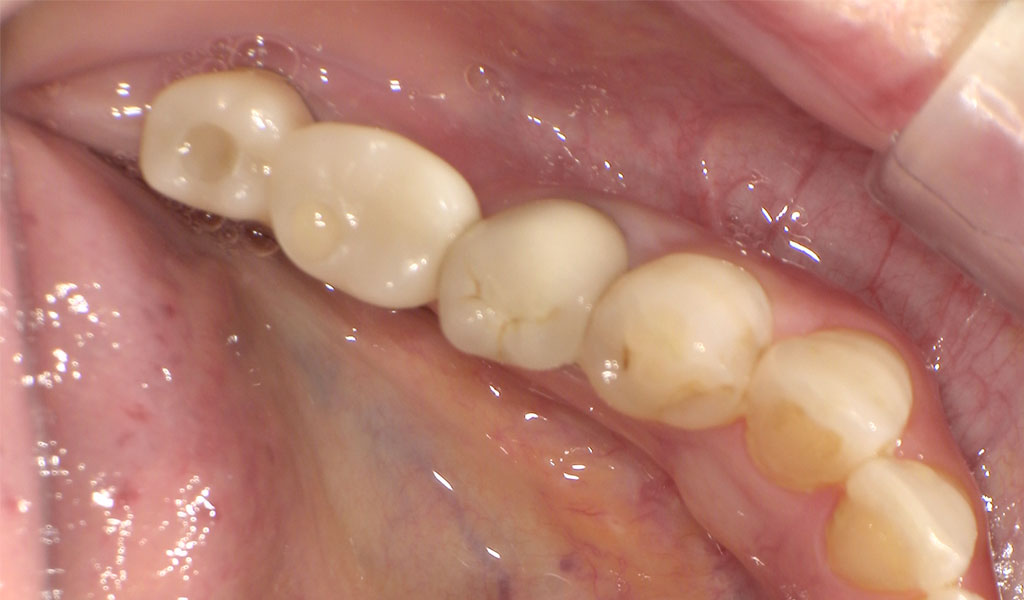

After1

フラップレス手術にて、左下6,7番の骨にインプラントを埋め込みました。

インプラントと骨がしっかり結合するまで3ヶ月待ち、また、歯周内科による治療が終わった上で、インプラントの上に人工の歯を被せる治療を行いました。